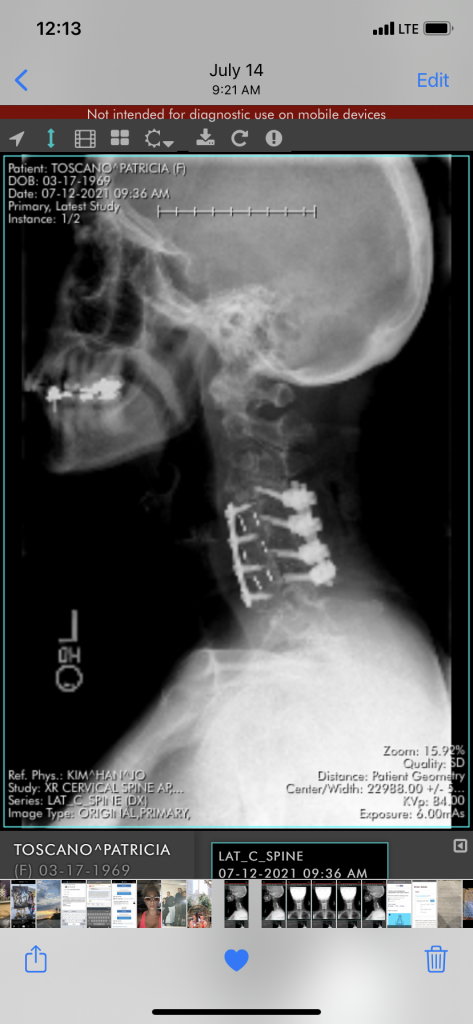

Spinal Fusion Surgery

I had been paralyzed in February, and was in a speechless place for three days! I was saved by Dr . Kim! He was the only doctor to make a blessed decision to save my life! With the help of the hospital staff as well as a social worker, it was all made possible! I’m stronger then ever! A true miracle! Thank you Dr. Kim! I don’t know the words to express the grateful breath I wake up to everyday! I have joy in my heart every breath I take I’m grateful for you. You gave me my active life just like you said! Dr. Kim is a godsend! Truly a beautiful soul of a human being! I’m off pain medication after 8 years of a cervical spine problem with nerve and brain injury! Dr Kim fixed a percentage of it I feel. I truly have a beautiful journey forward.

This experience has been severely traumatizing for me. I believe I truly have my life back because Dr. Kim is a loyal soul of a doctor! Blessed to have you in my heart for the rest of my days. Yesterday was 6 months from my surgery, and I will do my best to stay active. It feels wonderful to have no pain, as there are many challenges with the nerves that trigger brain issues. I’m so much better. I have about 6 months to pay attention, and it should get better as the days go by. The cold is being a problem, so I’ll stay home this winter. Blessed to be alive! I’m on a journey one day at a time. Dr. Kim saves! Thank you!❤️